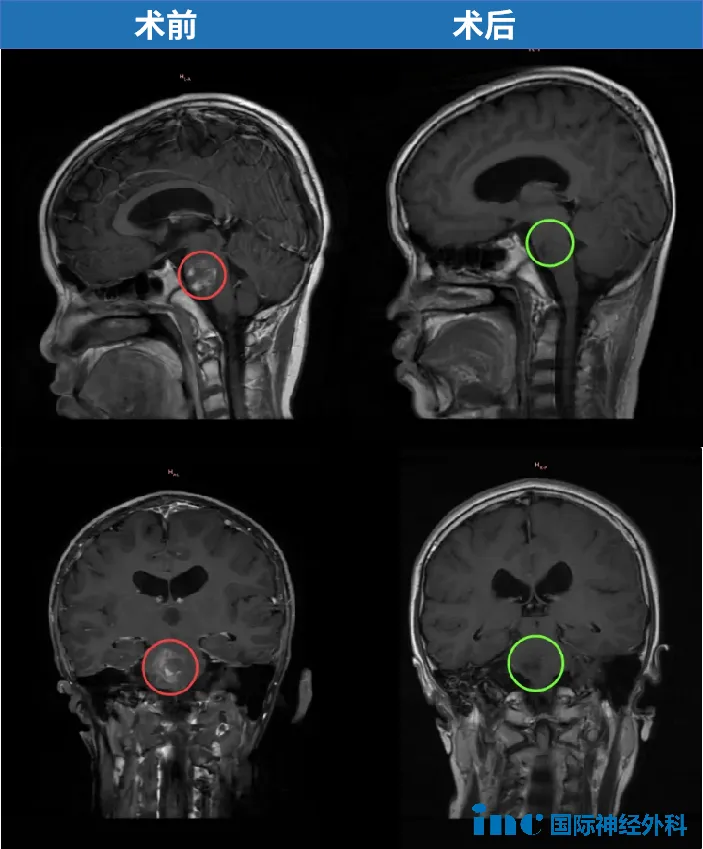

中脑胶质瘤手术案例

脑桥胶质瘤手术案例

延髓胶质瘤手术案例